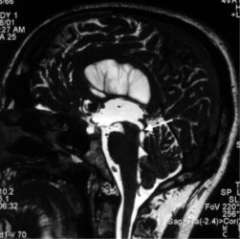

- The diagnosis of aqueductal stenosis is best made by magnetic resonance imaging (MRI), particularly using a special constructive interference in steady state (CISS), or fast imaging employing steady-state acquisition (FIESTA) sequence. CISS imaging is not available at all imaging Centers.